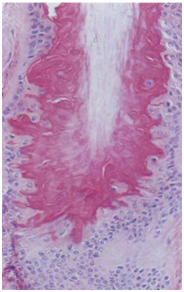

Гистологические исследования кожи при алопеции Х указывают на наличие изменений в волосяных фолликулах и эпидермисе (эпидермальный и фолликулярный ортокератозный гиперкератоз, дилатация волосяных фолликулов, избыточная трихолеммальная кератинизация, эпидермальный меланоз, телогенизация волосяных фолликулов). Могут наблюдаться некоторые особенности фолликулярной дисплазии, такие как переполненные по причине ортокератозного гиперкератоза волосяные фолликулы, которые образуют причудливые фигуры, напоминающие щупальца осьминога, а также аномалии, относящиеся к меланизации волос и волосяных фолликулов. Все эти изменения свойственны большинству эндокринологических проблем (таких, как гипотиреоз и ГАК), а потому биопсия и гистология кожи вряд ли смогут приблизить врача к постановке такого диагноза. В связи с этим алопеция Х – некий «диагноз исключения», который устанавливается посредством дифференциации всех иных причин, способных приводить к спонтанной алопеции. Достоверно дифференцировать алопецию Х и другие заболевания с помощью гистологического исследования на 100% невозможно. Однако при этой патологии обнаруживается больше волосяных фолликулов в форме «языка пламени», и эта форма более выражена, чем при других дерматопатиях. Иногда такие фолликулы диффузно распределены в биопсийных образцах. Они характеризуются наличием больших «шипов» слившегося кератина, пронизывающих наружное корневое влагалище вплоть до стеклянной мембраны волосяного фолликула, что придает гистологической картине вид пламени3. Как уже было отмечено, такие фолликулы могут отмечаться и при других, например эндокринных, дерматозах (фото 4).